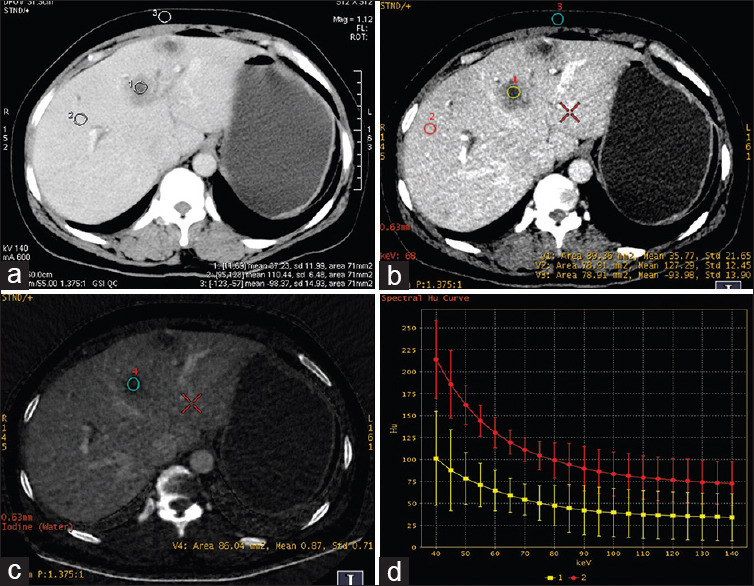

Materials and methods: From October 2012 to October 2018, 46 patients (28 males and 18 females) with CRCLM received GSI followed by chemotherapy were retrospectively reviewed. The patients were divided into a response group (n = 32) and a nonresponse group (n = 14) according to the tumor response to chemotherapy. The iodine concentration images and virtual monoenergetic images (VMIs) with an optimal contrast-to-noise ratio at the arterial phase (AP) and portal venous phase (PVP) were obtained by GSI viewer. The iodine concentration value and computed tomography (CT) value on VMIs and slope of spectral attenuation curves of all lesions were compared. A logistic regression analysis was used to determine the predictor of chemotherapy response.

Results: The difference of extrahepatic metastasis (P = 0.001), CT value on 68 keV VMIs at the AP (P = 0.005) and PVP (P = 0.001), slope of CT value attenuation curves at the AP (P = 0.013) and PVP (P = 0.001), and iodine concentration value at PVP (P = 0.003) between the response and nonresponse groups were statistically significant. The CT value of the 68 keV VMIs (OR: 1.206; 95% confidence interval [CI]: 1.021-1.425, P = 0.027) and the iodine concentration value at PVP (OR: 1.952; 95% CI: 1.034-3.684, P = 0.039) were independent prognostic factors for predicting chemotherapy response.

Conclusion: Baseline GSI may help predict the response to chemotherapy and provide a good tumor-response indicator through single-energy CT value of 68 keV at the PVP and iodine concentration.